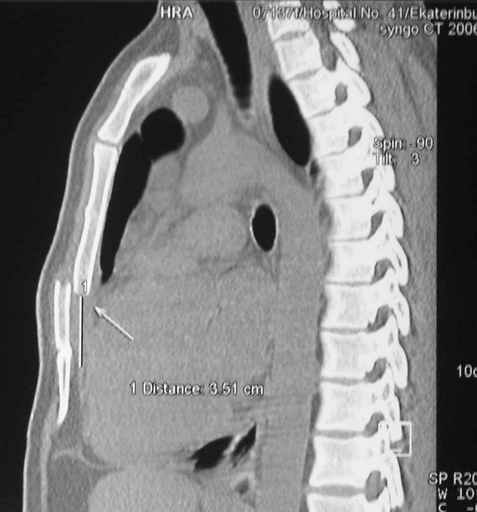

Глубокоуважаемые коллеги, Обратились за советом коллеги из соседней больницы. Мужчина 30 лет, в автоаварии ударился грудью об руль. После травмы 3 недели. Определяется отчетдивая подвижность на месте перелома. Снимок в приложении. Пока обсуждали варианты - LCP (какую?) или спицы. Открывать зону перелома или нет? Что посоветуете?

Пару лет назад коллега из грудной хирургии направил больного с хроническими жалобами на боли по поводу ложного сустава грудины.

Оперировали вместе с грудным хирургом и в нашем случае главной причиной была болезненность. Во время операции приняли все меры предосторожности недопущения прокола средостения (см. на 4 снимке близкий контур сердца!!)

Ложный сустав зафиксирован двумя пластинами 2.4 мм (locking plate) позаимствованными из челюстно-лицевой хирургии, с костной пластикой, все остальные пластины мне показались слишком толстыми, грубые для грудины или отсутсвовали возможности создания угловой стабильности.

Рентген снимки во время операции и последние сделаны на днях.